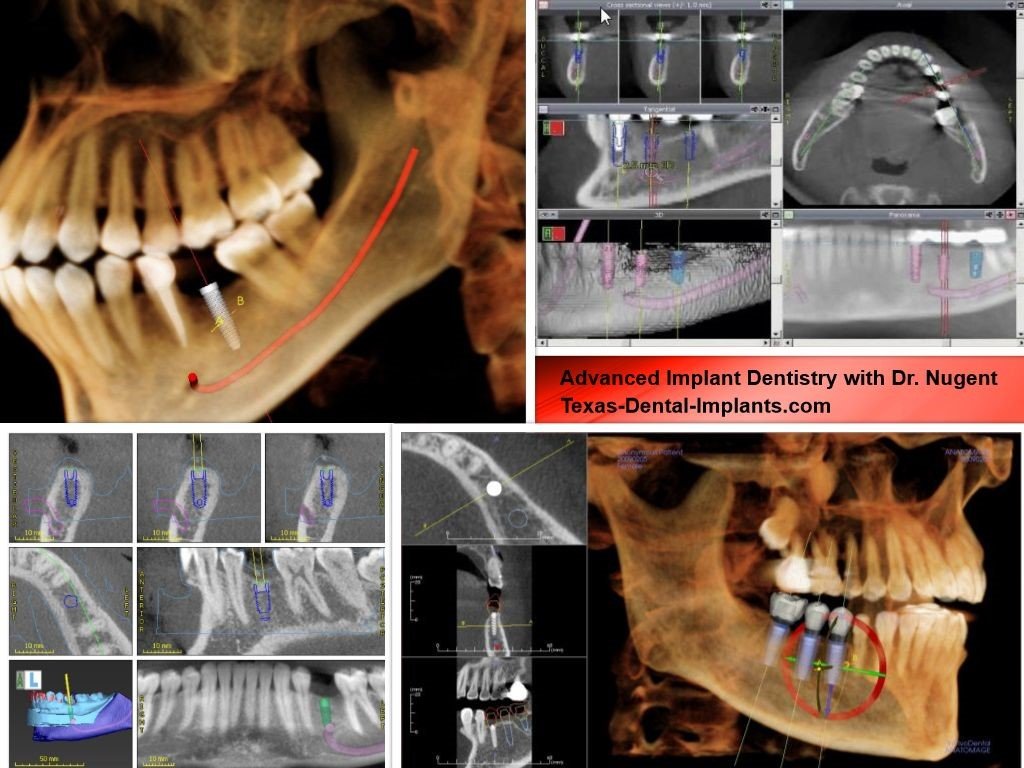

1. CBCT (Cone Beam Computed Tomography) for 3D Bone Analysis

CBCT is the foundation of digital implant planning, providing high-resolution, three-dimensional imaging of the patient’s bone structure, sinus positioning, nerve pathways, and soft tissues. Unlike traditional panoramic X-rays, CBCT scans offer:

- Accurate bone density mapping, helping clinicians determine whether additional procedures like bone grafting are required.

- Precise anatomical visualization, ensuring implants are placed in an optimal location to avoid nerves and sinus cavities.

- Improved prosthetically driven planning, where implant positioning is determined not just by bone availability but by final restoration requirements.

CBCT imaging is seamlessly integrated into digital planning software, allowing for precise implant trajectory simulation before surgery.